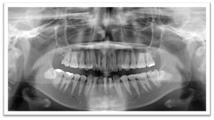

通常のレントゲンとCTとの比較

通常お撮りしていた全体像が解るレントゲンです。

お口全体の情報がかなりの確率で把握出来ます。

通常の治療の場合はこちらのレントゲンで十分です。